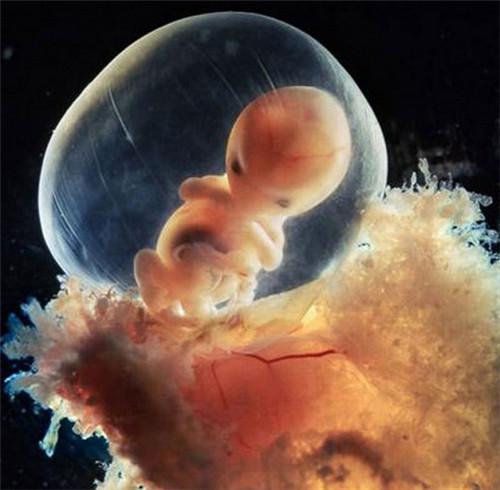

22天后,胚胎发育

6812778217.jpg

胎儿的心脏

6075248505.jpg

受精后第28天

6813172132.jpg

5周大的胎儿。此时胎儿只有大约9毫米长,面部正在发育,嘴巴、鼻孔和眼睛正在形成.更多精彩资讯,请关注微信平台a2676333820

6371347578.jpg